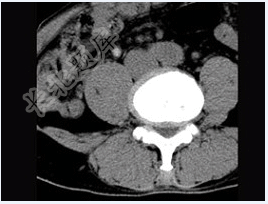

- 单项选择题男,45岁,腰痛,请结合所提供图像,选择最佳答案( )

A、前纵韧带钙化

B、椎间盘膨出

C、椎间盘突出

D、腰椎骨质增生

E、椎间盘未见异常